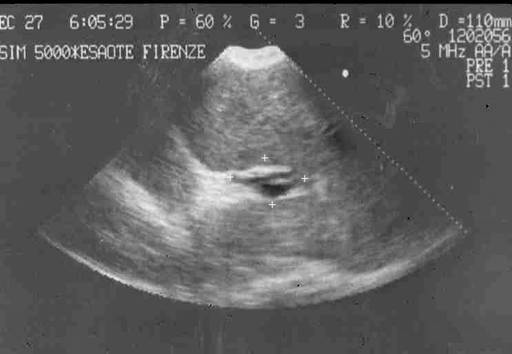

Современная ультразвуковая диагностика позволяет не только оценить структуру и размеры печени, селезенки, но и оценить скорость и характер кровотока по сосудам воротной системы. При болезни Бадда-Киари УЗИ с допплерографией позволяет выявить непроходимость печеночных вен. При циррозе печени при УЗИ хорошо виден узловой характер изменений в печеночной паренхиме. «Портальная кавернома» - кавернозное расширение гепатопетальных коллатералей при портальной гипертензии - наглядно определяется при УЗИ.(Рис. 5) Взаимоотношение сосудов брюшной полости и характер кровотока по ним, выявляемые при УЗИ с допплерографии, очень важно для планирование возможностей оперативного вмешательства.

Рисунок 5. «Портальная кавернома» - конгломерат коллатералей в воротах печени на месте ствола воротной вены у ребенка с внепеченочной портальной гипертензии. Данные УЗИ.